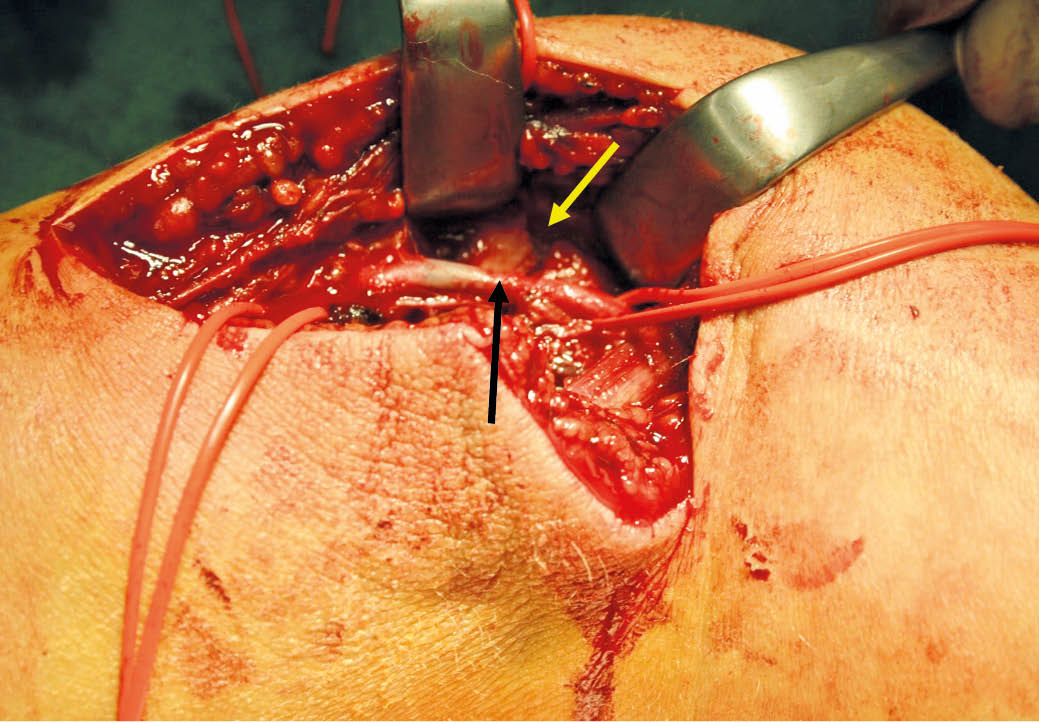

Unter diaphanoskopischer Kontrolle (Abb. 5) mussten die 2 weiteren epigastrischen Arbeitstrokare etwas mehr rechtsseitig positioniert werden. Intraoperativ (Abb. 6) stellte sich die Gallenblase sowohl akut als auch chronisch entzündlich verändert dar. Die Leber zeigte makroskopisch venöse Malformationen sowie einen beginnend kleinknotigen Parenchymumbau. Die laparoskopische Cholezystektomie verlief ohne Komplikationen, auf die Einlage von lokalem Drainagematerial konnte verzichtet werden. Die pathohistologische Aufarbeitung (Abb. 7) zeigte eine chronisch-fibrosierende Cholezystitis mit Gallenblasenwandverdickung ohne Anhalt für Malignität.

Abb. 5: Intraoperativer laparoskopischer Befund des Hämangioendothelioms der Rumpfwand linksseitig sowie auf dem Ligamentum triangulare sinistrum. Nebenbefundlich kleiner von-Meyenburg-Komplex im Lebersegment-II/III-Übergang bei Leberzirrhose